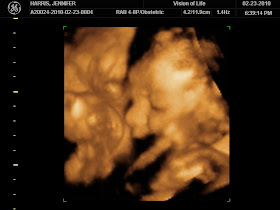

This afternoon we had our 3D/4D ultrasound for baby H #2! We went to the same place as we did with Austin and at 30 weeks just like we did with Austin....BUT this baby didn't quite cooperate the way Austin did...

The tech said baby had enough room in there but for some reason he wanted to be curled up in a little ball the ENTIRE time! From what we saw, he looks a lot like his big brother, but it was kind of hard to get the greatest pictures because he had his little knees in his face the whole time.

We watched our sweet babe wiggle around for over 30 minutes but I could have sat there all evening! He was being so active and we just kept waiting for him to show us his little face, but he wanted those little arms and knees by his face the whole time.

So squished in there, but we can still tell he has his daddys and big brothers nose!

Our best face shot